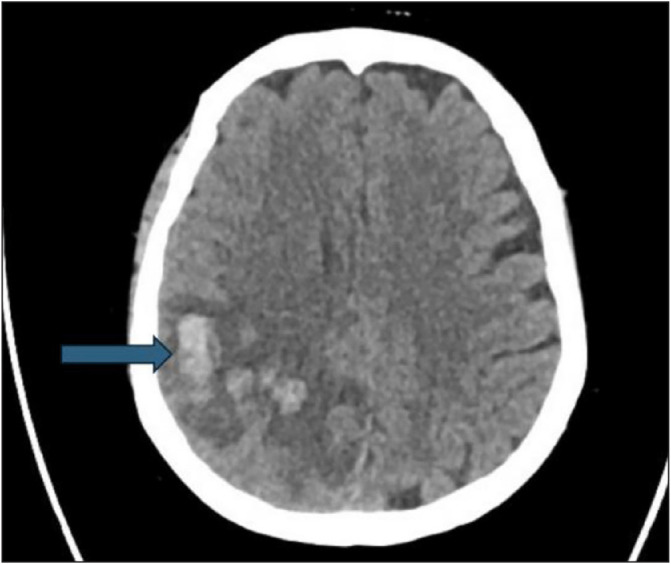

Case presentation: We report a unique case of CVST induced by HIT in a patient with an established diagnosis of MG. Following plasma exchange therapy, which included heparin administration, the patient developed symptoms indicative of CVST. Diagnostic imaging confirmed thrombosis in the cerebral venous sinuses. Management involved the immediate discontinuation of heparin and the initiation of fondaparinux, leading to effective anticoagulation and clinical improvement.

Abstract Image